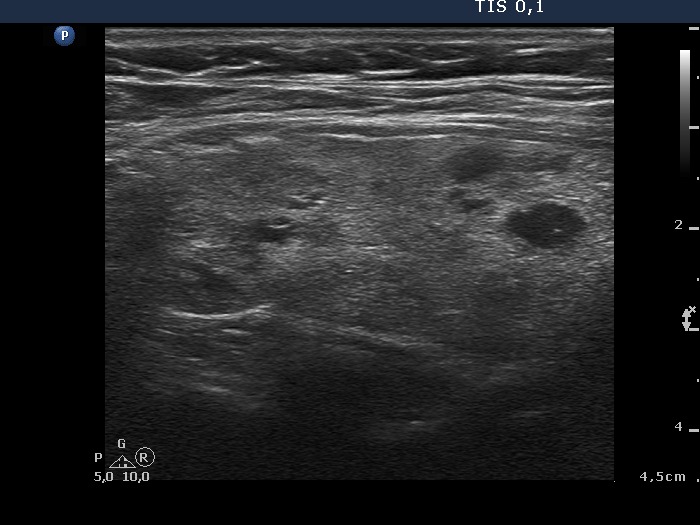

100 consecutive patients with thyroid nodule - Case 26.

8 months after sclerotherapy (ultrasonographic picture 5)

Left lobe, longitudinal scan.